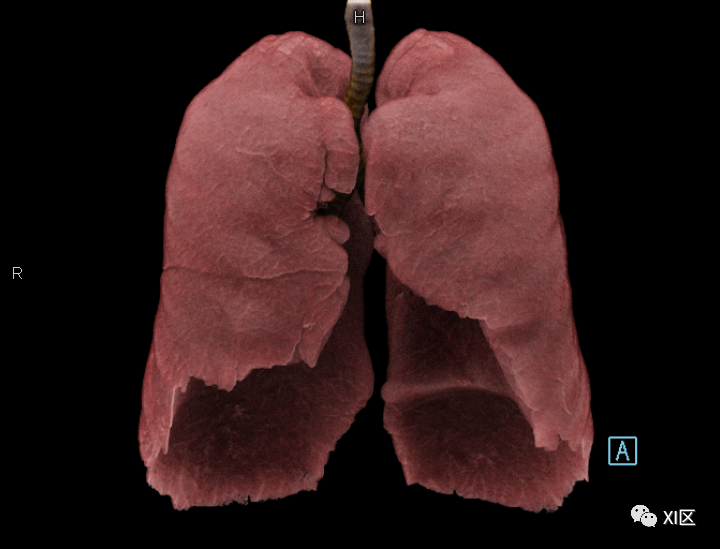

牛蛙三维重建,肺几乎占了整个胸腹腔

首先,

我们看一下牛蛙的肺

这只牛蛙的肺体积非常大

测量发现

体积为38.41ml

之前我们知道了这只牛蛙的总体积

简单计算后发现

牛蛙的肺占全身体积的

13.14%

牛蛙志愿者的肺部CT为38.41ml

作为对比,正常体型的成年人

平静状态下

肺部体积约为全身体积的4%左右

可以说

牛蛙的肺比人大3倍以上

这么大的肺

肯定能存很多气

气足了

嗓门自然大一些

牛蛙肺部重建

作为对比,人类的肺部重建 SOMATOM Force扫描 cVRT重建

人类胸部Cinematic Rendering重建